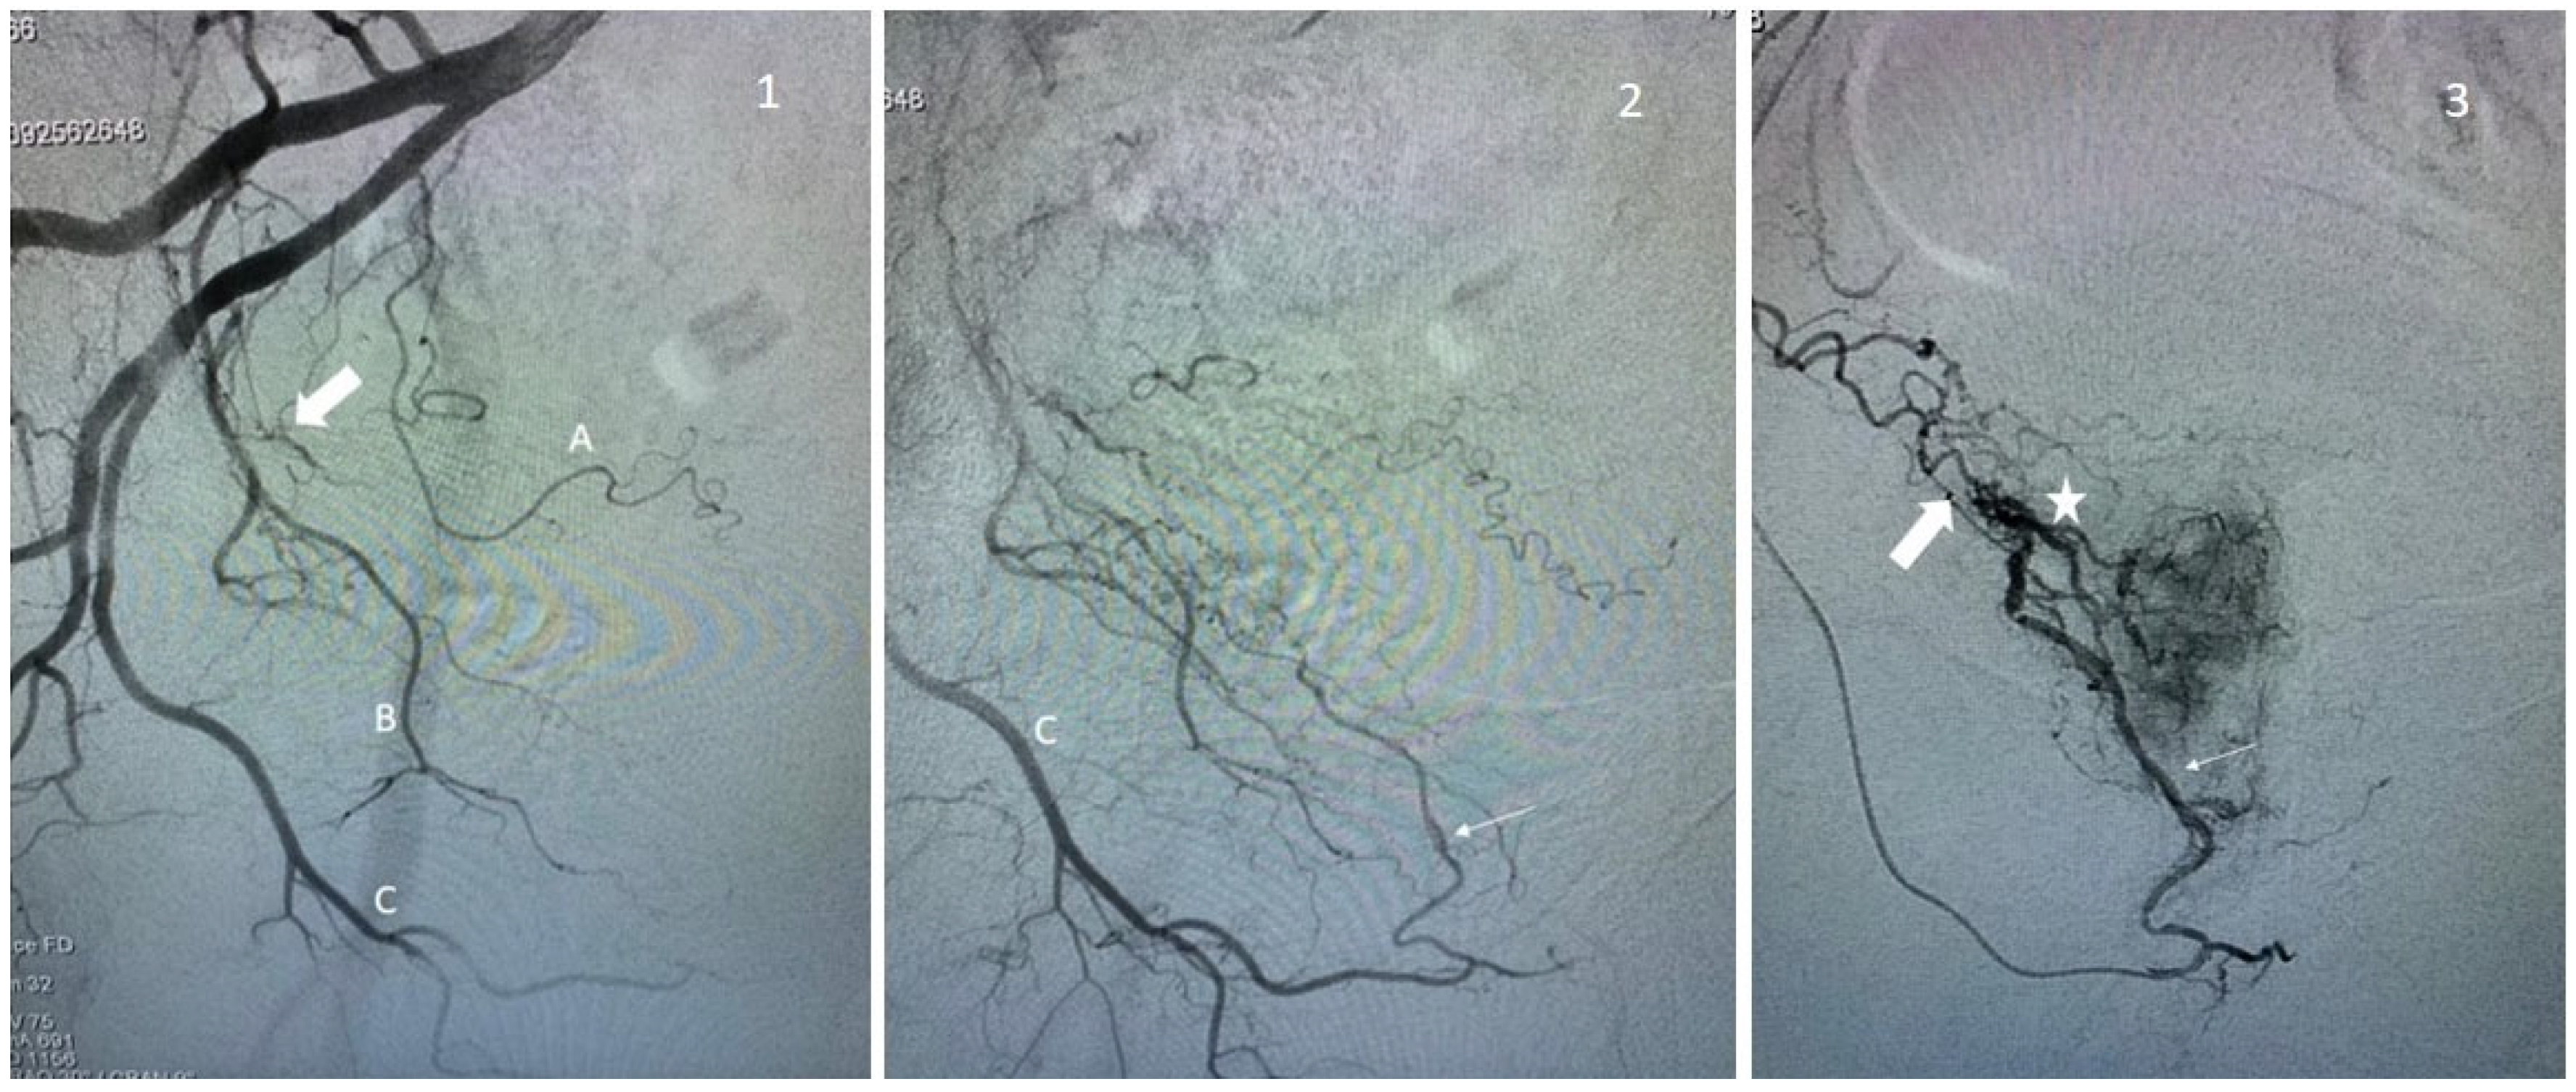

Figure 3.

Examples of prostate artery occlusion and revascularization of the prostate via a distal pudendal/prostatic apical shunt. Image 1: Internal iliac angiography demonstrating a vesical inferior artery (A), an obturator artery (B), and an internal pudendal artery (C). Note the occluded prostatic artery (arrow). Image 2: Supraselective angiography of the internal pudendal artery (C) showing a connexion with the prostatic artery via an apical shunt (thin arrow). Image 3: Retrograde catheterism of the prostatic artery (thin arrow) and opacification demonstrating opacification of the prostatic central branch (star) and confirming occlusion of a proximal prostatic artery (large arrow).